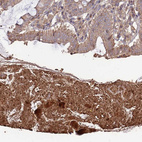

Immunohistochemical staining of human prostate shows moderate to strong cytoplasmic positivity in smooth muscle cells.